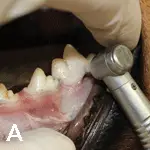

Use a #8 round bur in a water-cooled high-speed handpiece with light pressure to remove the alveolar bone and expose the furcation.

Round burs range in size from #2 to #8, increasing in size with the number. Bur size is selected based on the size of the patient.